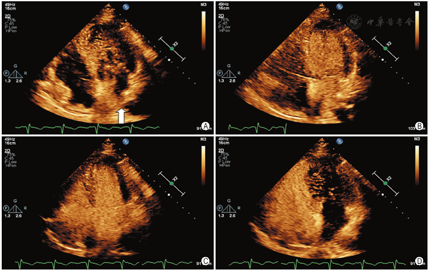

患者男,46岁,主因左上肢无力2个月余,加重1 d入院。既往高血压病史10年,高脂血症病史2个月。头颅MRI:右侧基底节、放射冠及额叶急性梗死灶。颅颈动脉CTA:轻度动脉硬化,以双侧颈总动脉分叉处为著。初步诊断:脑梗死(急性期),高血压1级,很高危,高脂血症。患者曾在外院行经胸超声心动图检查未见异常,为除外卵圆孔未闭右向左分流所致脑卒中,申请行右心声学造影检查。静息下左上肢静脉注入激活生理盐水,右心显影后左心内未见显影,随后行Valsalva动作激发试验,发现注射激活生理盐水后左房先于右房显影,且左房内微泡浓度短暂高于右房(图1)。更换为右上肢静脉注射激活生理盐水,静息下及Valsalva动作后均右心显影,左心未显影。鉴于上述结果,考虑左侧静脉连接异常,行经胸超声心动图检查,重点扫查胸骨上窝切面。在降主动脉左侧可测及异常静脉,宽约8 mm,与左无名静脉相通,汇入右侧上腔静脉,彩色多普勒血流显像示静息时异常静脉血流流入左无名静脉,Valsalva动作后可见异常静脉内血流短暂逆流,结合右心声学造影表现,考虑异常静脉为永存左上腔静脉,直接或通过左肺静脉汇入左房(图2)。患者行左房肺静脉CT证实永存左上腔静脉经左上肺静脉汇入左房(图3)。